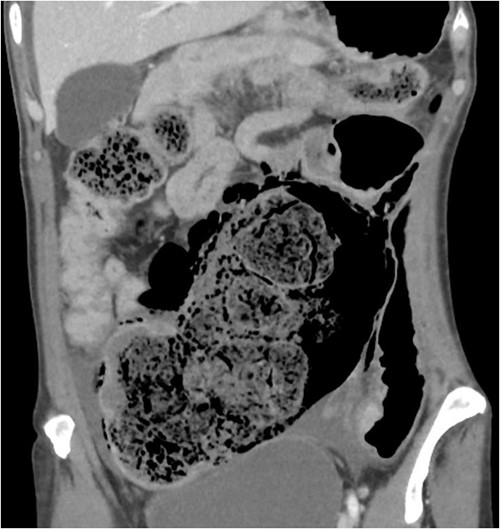

On CT of her abdomen and pelvis, there was a large volume of pneumoperitoneum and a massive sigmoid faecaloma suggestive of stercoral perforation associated with ischaemic changes (Fig. 1). She underwent emergency laparotomy, which identified a grossly dilated and redundant sigmoid colon impacted with a large, inspissated faecaloma >15 cm in diameter (see Figs 2 and 3). The perforation was identified in the mid to distal sigmoid colon with evidence of necrosis of the wall. A Hartmann’s procedure and extensive washout was performed. Post-operatively, the patient required vasopressor support for septic shock in intensive care, as well as granulocyte colony stimulating factor (G-CSF) to help in the management of her febrile neutropaenia. Her Clozapine was suspended for several days due to her neutropenia. She was given G-CSF to improve her neutropenia to improve her chances of survival as it known that immunocompromised patients with sepsis have worse prognosis [9]. Fortunately, the patient recovered well post-operatively and was discharged to rehabilitation on day 10.

Intraoperative findings of ischaemic stercoral perforation of the sigmoid colon.